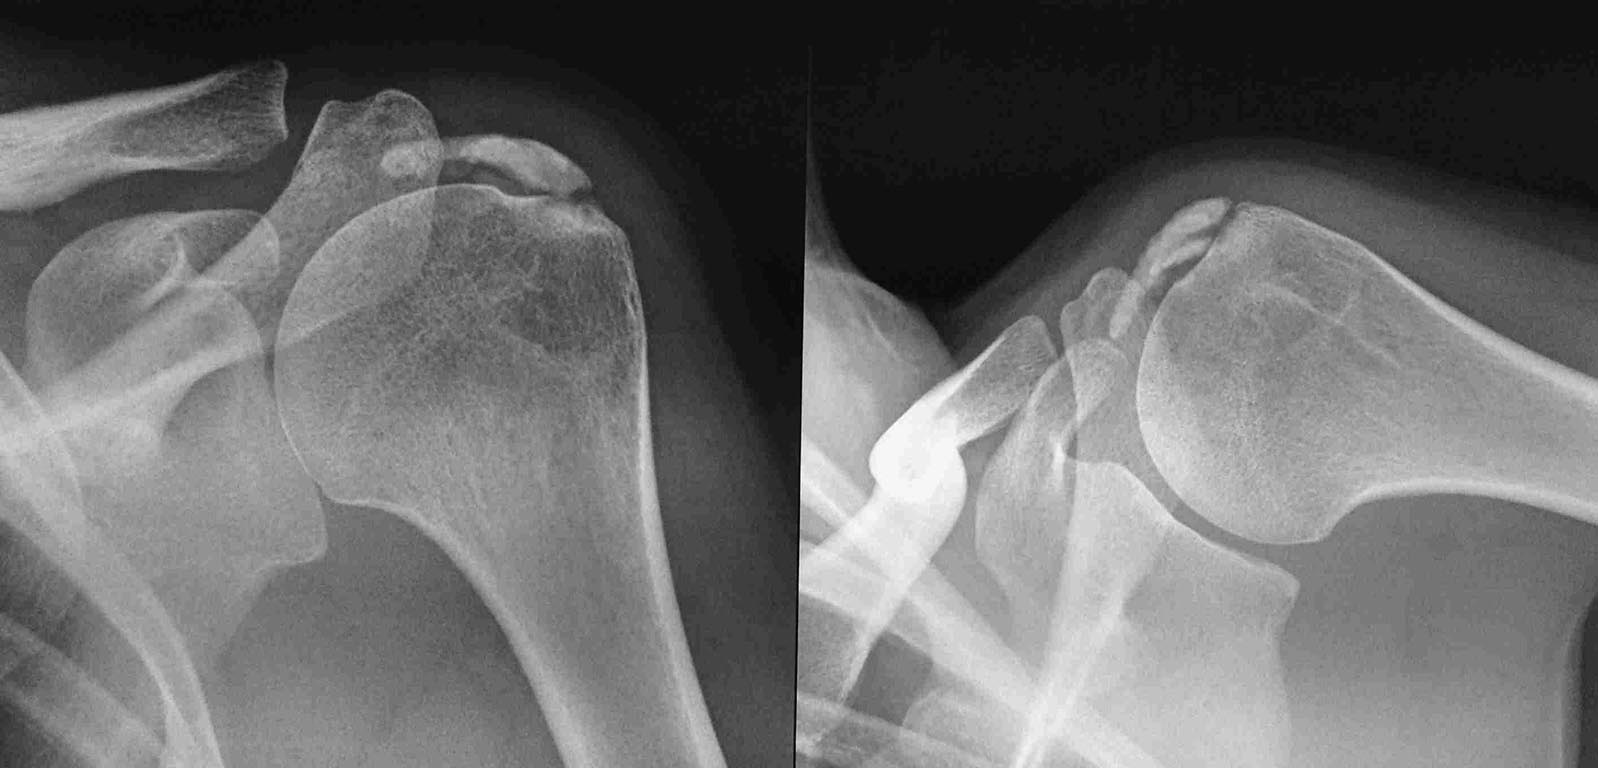

Здравствуйте уважаемые коллеги. вот возник вопрос. больная Е 36 лет

кальцинирующий тендинит с обеих сторон (на рентгенограммах одна

сторона). плотность по КТ 1400. несмотря на это перед тем как идти на

артроскопическое удаление депозита произведена попытка размыть

физраствором. вот что и получилось. объем движений в суставе полностью

восстановлен " на столе" через место депозита 2000мл раствора.

клинический результат понравился. и вот вопрос будет ли дальше нравиться

клинический результат, в смысле какова вероятность

рецидива при данной технологии. ведь остатки депозита в ротаторной

манжете. нигде не нашел результатов после артроскопии, там тоже остаются

какие-то элементы кальцинатов манжеты?